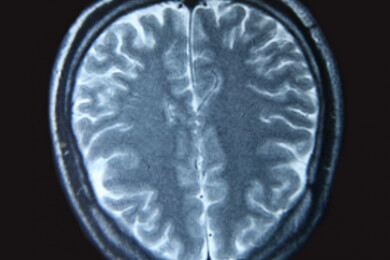

Der Neurologe führt im Rahmen seiner Diagnostik auch ein EEG durch und misst dabei die Hirnströme. Bei Verdacht auf einen Gehirntumor wird eine Magnetresonanztomografie angefertigt. Auf der Aufnahme ist der Tumor sichtbar.